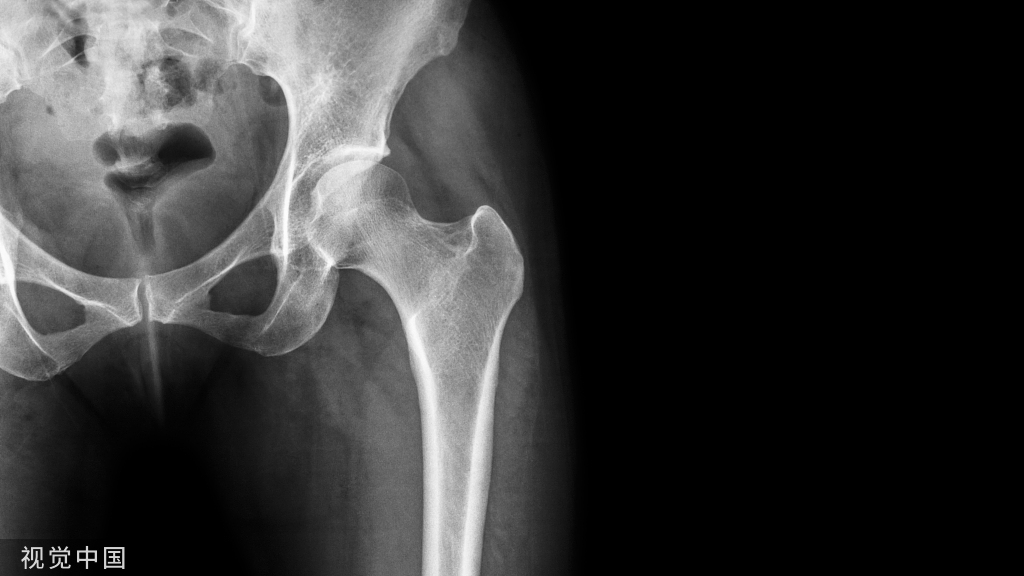

髋关节脱位主要分为后脱位和前脱位,80%都为后脱位

最常见的仪表盘类损伤常伴随后脱位,需要行X线进行脱位的确诊

后脱位有的是由旋转暴力,有的是由垂直暴力所引起

2、具体的临床表现内收、屈曲、内旋